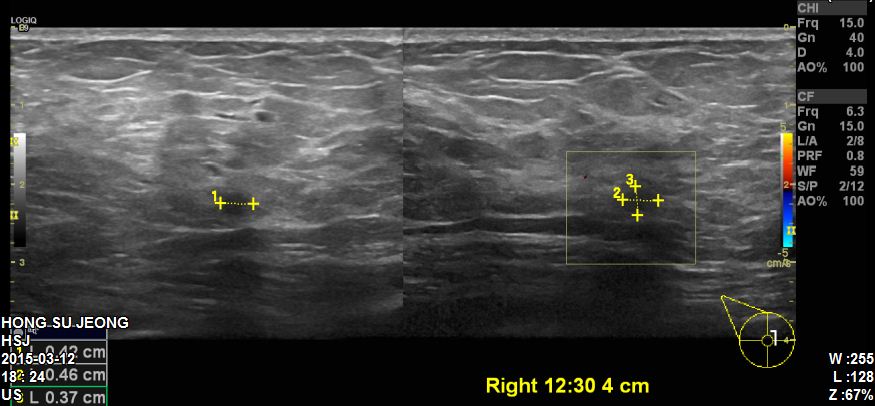

본원에 내원하신 60대 환자분이십니다.

유방초음파 시행 후 우측유방에 0.4cm의 혹 발견되어

조직검사 시행하였습니다.

결과상 침윤성유관암 진단되었습니다.